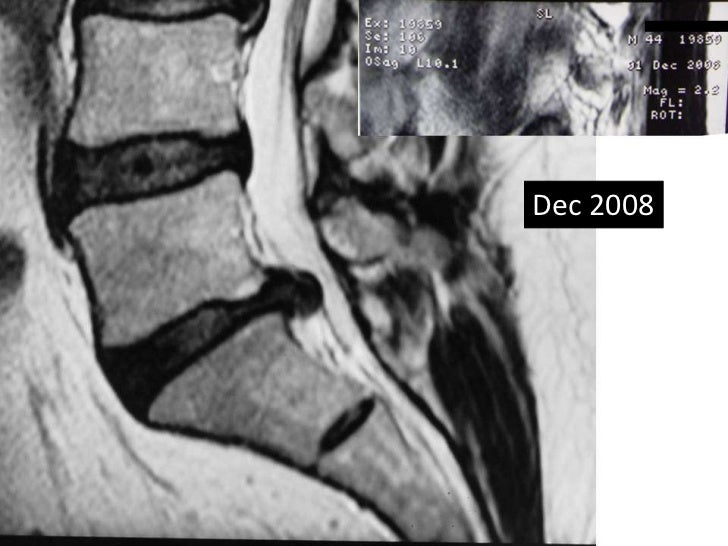

From www.semanticscholar.org

Figure 2 from Spontaneous regression of a large lumbar disc extrusion Lumbar Disc Extrusion Icd 10 disc extrusion is a type of intervertebral disc herniation that extends beyond the disc level and has a broader dome than a neck. Identify the etiology of lumbar disc herniations. Review the proper steps in the evaluation of lumbar disc herniations. this code is used to specify a diagnosis of other intervertebral disc displacement, lumbar region, which may. Lumbar Disc Extrusion Icd 10.